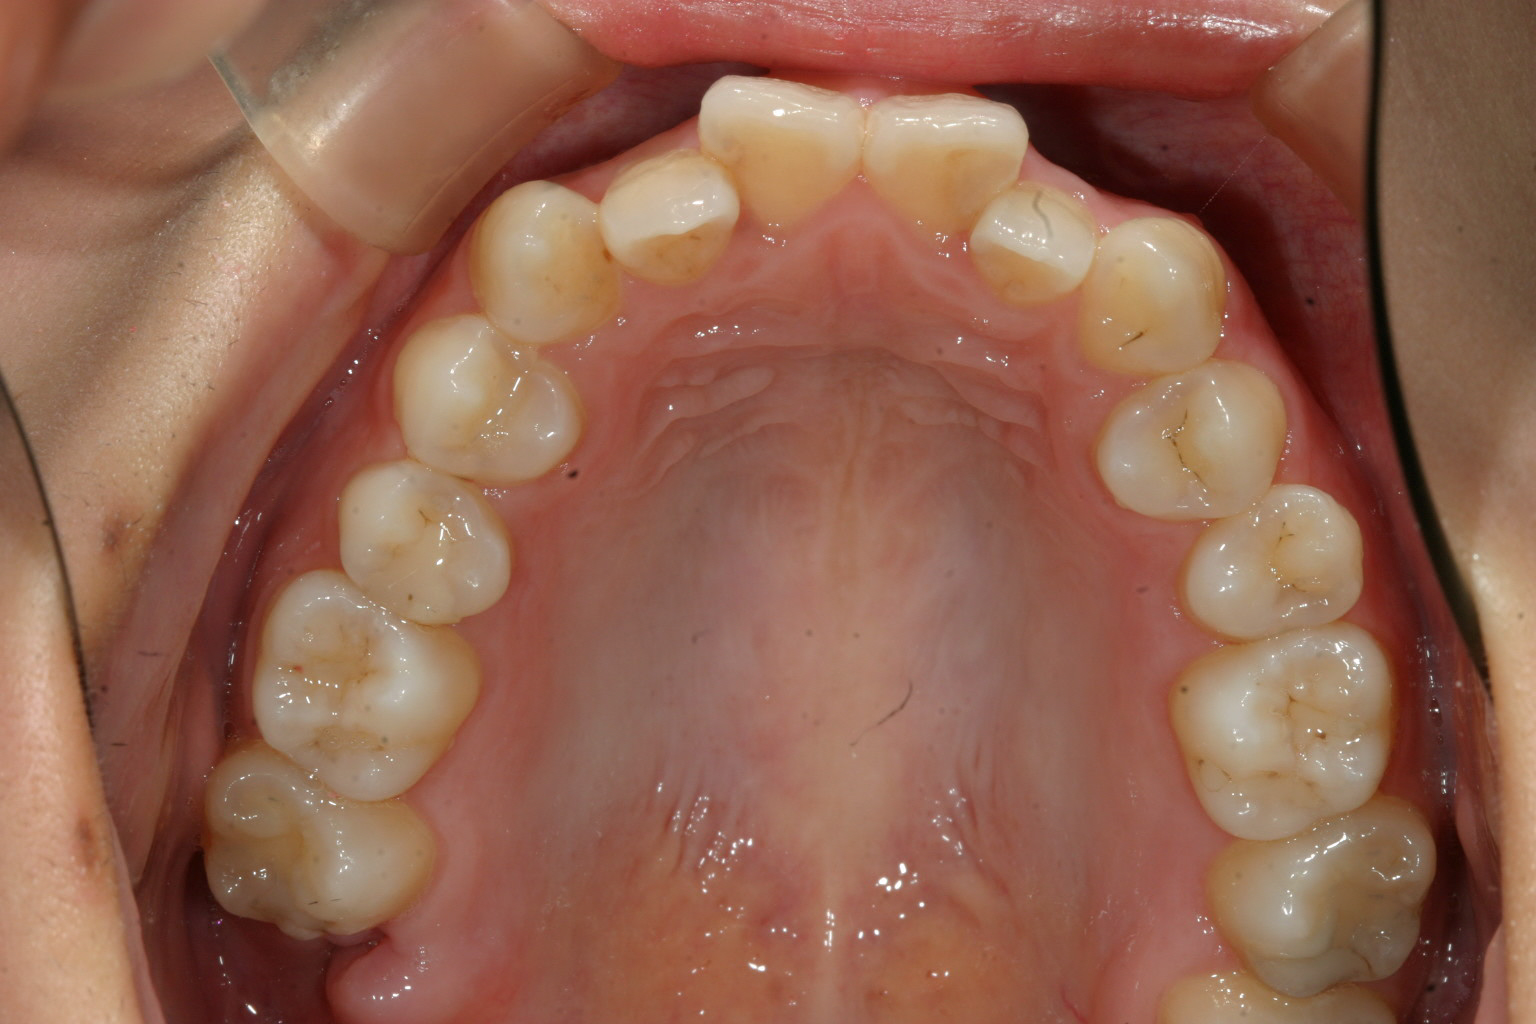

アーチが狭い為に前歯が並びきらずガタガタしてます。

下顎の少し叢生が有ります。

少し受け口ですね!